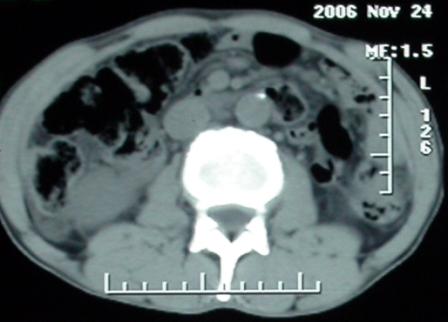

作者: rsyby 时间: 2006-11-28 22:41

标题: 上腹隐痛、饱胀、消瘦2-月。

增强ct所见【动脉增强期】